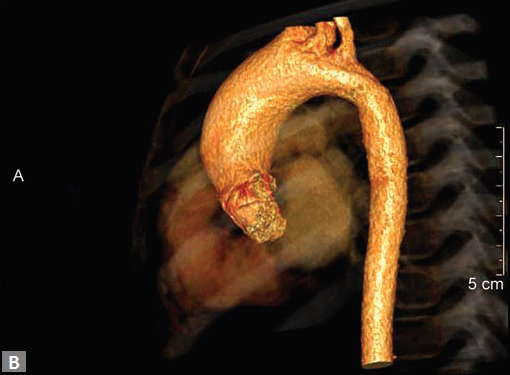

Any part of aorta can get affected by aneurysms. Focal

dilations can be saccular or fusiform. Atherosclerosis is

the most common cause. Tubercular and other infective

aneurysms, traumatic ones are also uncommonly seen. Size

of the aneurysm, proximity to origin of main vessels, relation

with branching and bifurcation, presence of mural thrombus

are the critical information sought on CT.

Contained leak, rupture are the feared complications.

Aortoenteric fistula is a rare but potentially catastrophic

complication. Aneurysmal dilation is common in ascending

aorta (Figs 19W to Y).

CT is also useful in surveillance of diagnosed aneurysms.

Figs 19A to Y (A to C) Scannogram (A), plain (B) and contrast study (C) show partial anomalous pulmonary venous connection; (D to F) Heterotaxy; (G) Aortic occlusion; (H and I) Aortic stents; (J) Aortic dissection with ‘Benz’ sign due to second dissection within the true lumen; (K, L and M) Aortic dissection with thrombus in pseudolumen following catheter angiogram; (N) Aortic dissection involving common carotid arteries and subclavian artery; (O, P, Q and R) Aortic dissection with right renal artery arising from true lumen and left renal artery from false lumen; (S, T, U and V) Stanford B dissection with extension Y to iliac vessels; (W to Y) Aneurysmal dilation of ascending aorta